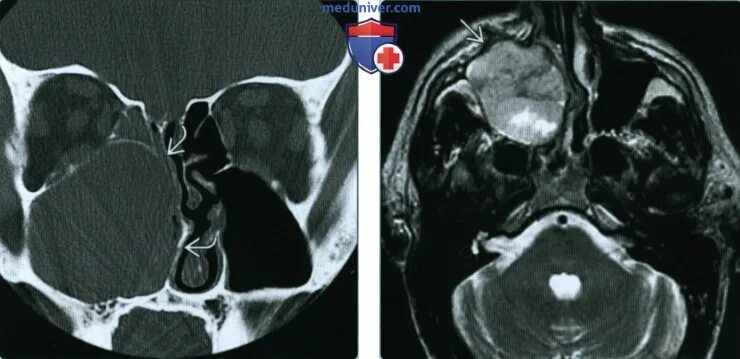

Аденокистозный рак слюнных желез